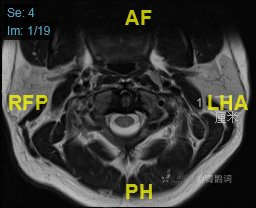

颈部磁共振平扫:

颈部磁共振平扫后增强: